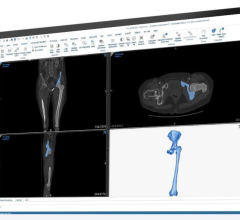

September 15, 2022 – Intelerad Medical Systems, a leading global provider of enterprise imaging solutions, announced its ...

Large-scale mergers and acquisitions are causing increased strain on IT teams responsible for consolidating and managing ...